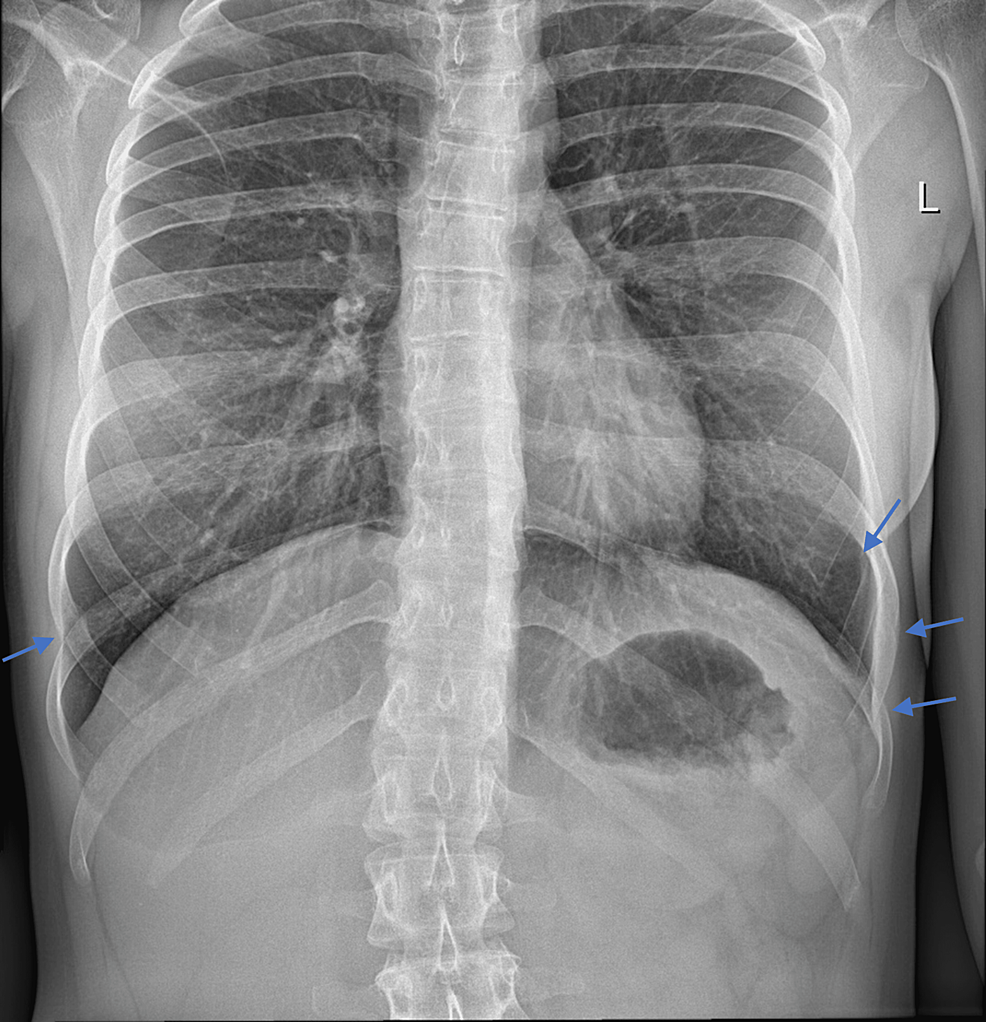

From www.cureus.com

Cureus CoughInduced Multiple, Bilateral, Asymmetrical Rib Fractures Rib Fracture With Coughing The pain is usually worse with movement, coughing, and deep breathing. When patients sustain a rib fracture, pain may preclude normal breathing or secretion clearing. Breathing risks from rib fracture. Middle ribs along the lateral aspect of the rib cage are affected most commonly. Multiple fractures were more commonly seen in older patients. Rib fractures can be very painful. Rib. Rib Fracture With Coughing.

Cureus Clinical and Radiological Aspects of Coughinduced Rib Rib Fracture With Coughing The pain is usually worse with movement, coughing, and deep breathing. A cracked rib is a type of rib fracture that can occur with a fall, car accident, sports injury, or violent coughing. Rib fractures can be very painful. Rib fractures are common injuries that occur most often following blunt thoracic trauma but can also result from severe. When patients. Rib Fracture With Coughing.